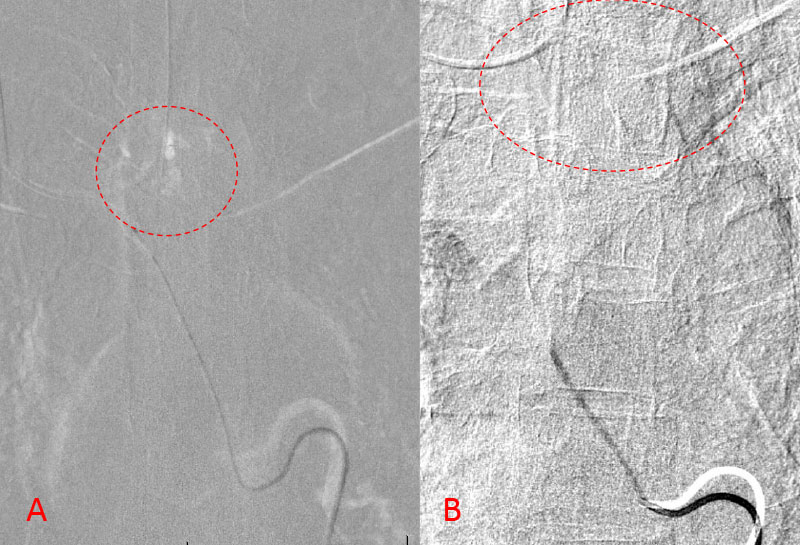

No spinal artery contributions were found to arise from this right T1-T3 pedicle. Superselective WADA testing was performed with Brevital injected through the microcatheter, which failed to elicit changes in the intraoperative monitoring, confirming safety to proceed with devascularization of this pedicle and tumor. This was performed with 100-300 micron particles achieving an excellent devascularization (Figure 3. A, B).

Figure 3. A and B) demonstrates selective PVA embolization with complete devascularization of the tumor on completed embolization